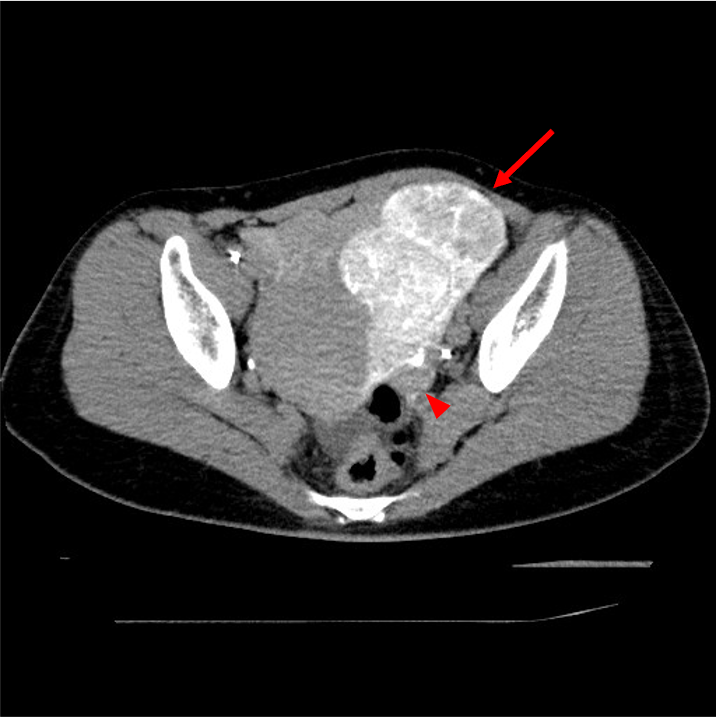

UAEの合併症には下腹部痛、術後感染、筋腫の子宮内腔脱落の他に、卵巣機能不全(45歳未満:0-3%、45歳以上:20-40%1))、非標的塞栓などがある。そのため、UAEを施行する際には、術前にMRIやCTにより子宮筋腫の局在や血管走行を確認してから治療を行う必要がある。我々は血管造影時に選択的子宮動脈造影と血管造影下CT (CT Uterine Arteriography :CTUA)を施行することにより、卵巣の濃染の有無や、拡張した子宮卵巣動脈吻合の有無、膣や子宮頸部の濃染の有無を確認し、UAEを施行している2)。Type1BやType3の子宮卵巣動脈吻合3)がみられた場合、UAEにより塞栓物質が子宮卵巣動脈吻合に流入し、卵巣機能不全に陥る可能性がある。そのためCTUAにより子宮卵巣吻合の分岐を確認し、子宮卵巣吻合のType分類を行い、子宮卵巣吻合が太く、卵巣への血流が豊富な場合(Type1B,Type3)には、子宮卵巣動脈吻合のコイル塞栓を施行している。CTUAを施行することにより、塞栓物質の非標的塞栓や子宮卵巣動脈吻合への塞栓物質の流入を防ぎ、安全にUAEが可能である。

子宮動脈塞栓術施行後には単純CTを撮像して、目的の子宮筋腫への造影剤の貯留があるかで塞栓範囲を確認している。